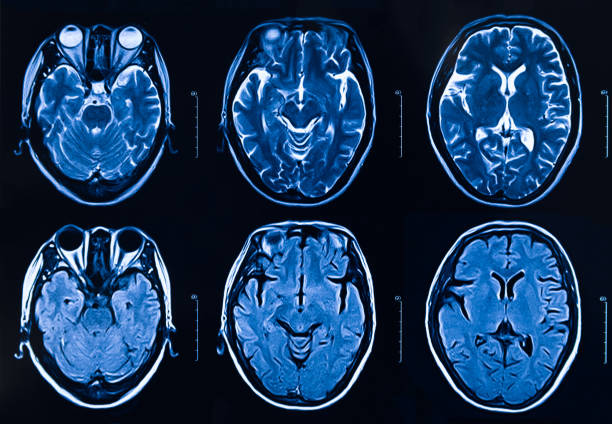

圖1:每個(gè)間充質(zhì)干細(xì)胞治療患者按組的原始非對(duì)比計(jì)算機(jī)斷層掃描和分割結(jié)果

本研究納入2018年1月1日至2020年10月31日發(fā)病168小時(shí)內(nèi)發(fā)生急性ICH的患者。間充質(zhì)干細(xì)胞被靜脈注射給9名患者(5名女性,4名男性),平均年齡(范圍)為61(36-84)歲。表1總結(jié)了人口統(tǒng)計(jì)學(xué)和臨床??特征 。出于描述目的,患者按照入組順序獲得編號(hào),并連續(xù)分配到三組中的一組,每組三人。根據(jù)模型 2 分割,ICH體積范圍為0.1至54.9mL(平均ICH體積為23.5mL)。5例ICH累及局部腦葉,其余則位于基底節(jié)或外囊深處。在三名患者中,ICH位于丘腦(圖1),在一名患者中,血腫位于多個(gè)腦結(jié)構(gòu)(即尾狀核、殼核和蒼白球)。平均而言,MSC在ICH后3天進(jìn)行注射。